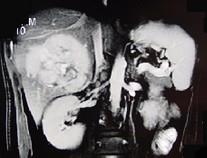

问题 男,36岁,腹胀、消化不良、消瘦、中上腹痛,影像检查如下图,最可能的诊断是 ( )

选项 A.胃间质肉瘤并肝转移 B.胃间质瘤并原发性肝癌 C.内胚窦瘤肝转移 D.胃淋巴瘤伴原发性肝癌 E.胃间质瘤并肝血管瘤

答案 A